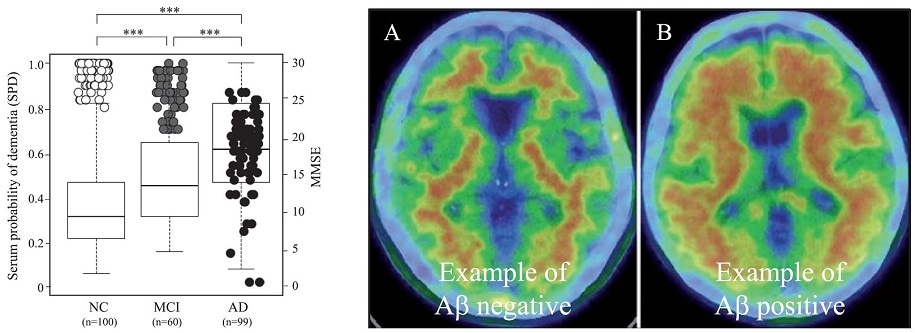

Left: The graph shows blood peptide levels (boxes) in the three groups and how higher levels of the peptides coincide with lower MMSE (cognitive) scores (circles). Right: An example of a healthy brain without Aβ, the toxic protein (A) and an AD brain with Aβ (B). Patients with Aβ-positive brains also had higher blood peptide markers.

The blood peptides of these three groups did indeed appear different, with a set of four specific peptides showing the most varied patterns. These peptides appeared to be high in the AD patients, moderate in the MCI patients, and low in healthy individuals. As expected, these peptide levels also coincided with each individual’s cognitive performance on a clinical test. Individuals with higher peptides did worse on the test. When some individuals were subjected to brain scans, it was found that AD patients showing an accumulation of toxic proteins in their brains also had high peptides in their blood. Thus, patterns of the four peptides in the three groups were in sync with the other detection tests. Finally, a deeper delve into the biology of these peptides hinted that they were linked to inflammation in the brain.